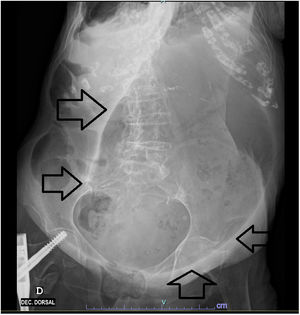

Analytically, he had leucocytosis, acute kidney injury, elevated troponin (973.2ng/l – reference value 0–15.6ng/l), pro-BNP (16407pg/ml – reference value 0.0–125pg/ml) and C-reactive protein (8.95mg/dl – 0.0–0.5mg/dl). Electrocardiogram with atrial fibrillation, with no apparent acute pathology. Radiography of the abdomen with marked gastric distention with the presence of air-fluid levels (Figs. 1 and 2).